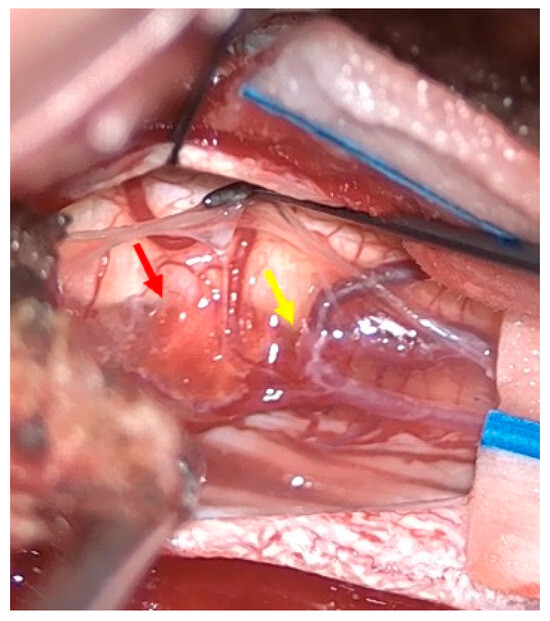

The patient was positioned prone, and a midline incision was performed, followed by bilateral muscle dissection and laminoplasty at T11–T12 using a piezoelectric osteotome (Mectron s.p.a—Carasco, Italy) [Figure 2]. Under the operating microscope, a dural opening was made, exposing the lesion, which appeared as an exophytic protrusion from the surface of the left posterior spinal cord, surrounded by a vascular malformation resembling a dural arteriovenous fistula (SDAVF) with multiple arteriovenous malformations on the pial surface [Figure 3]. Coagulation and disconnection of the fistulas were performed first by using bipolar cautery and scissor separation [Figure 3]; a detailed image of the hemangioma and the associated fistula is shown [Figure 4]. An incision was made around the lesion, which exhibited firm consistency. Due to the inability to remove the pathological tissue without traction, an ultrasonic aspirator was used for the microsurgical resection. Meticulous hemostasis was achieved. The dura mater was sutured, and a laminoplasty was performed using plates and screws. Standard wound closure was performed.

Figure 3.

Intraoperative findings. Upper left: Visualization of the hemangioma (red arrow) associated with the vascular malformation resembling a dural arteriovenous fistula (yellow arrow). Upper right: Sealing of the fistula using bipolar cautery. Bottom left: Macroscopic color change following fistula closure. Bottom right: Macroscopic appearance following hemangioma removal.